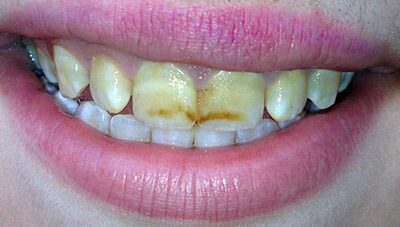

Фото эрозивной, эндемической, штриховой формы

Фото 1. Эрозивная форма флюороза, эмаль значительно истончена, на ней наблюдаются ямки.